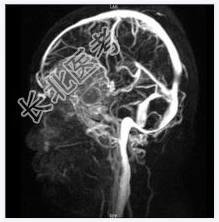

- [材料题] 患者女,55岁,视力下降数月。查体:视力下降,余神经体征阴性。

- 简答题1、诊断及依据是什么?

- 简答题2、鉴别诊断有什么?